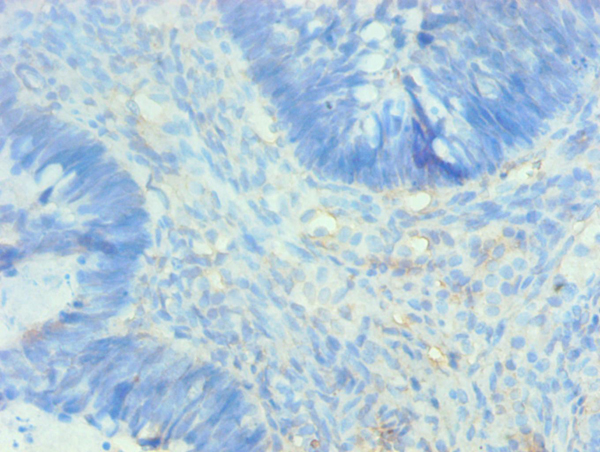

Immunohistochemistry

IHC (Immunohistochemistry)